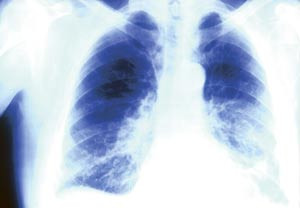

Lungeemboli kan være en vanskelig diagnose å stille, men nå har nederlandske forskere foreslått en enklere fremgangsmåte.

Ifølge den forenklede algoritmen vurderer man først sannsynligheten for at det foreligger lungeemboli eller ikke ved hjelp av en validert klinisk metode. Basert på denne kategoriseringen gjennomgår pasienten så D-dimertest eller CT-undersøkelse (1).

Studien omfattet 3 300 pasienter med mistenkt lungeemboli. Hos 1 000 av dem ble det ikke gjennomført behandling mot lungeemboli fordi D-dimertesten var normal og diagnosen lungeemboli ble ansett som usannsynlig. I løpet en tre måneders oppfølgingsperiode var det bare fem av disse personene som utviklet venøs tromboembolisme. 1 400 personer med negativ CT-undersøkelse ble heller ikke behandlet, av disse utviklet 18 venøs tromboembolisme.